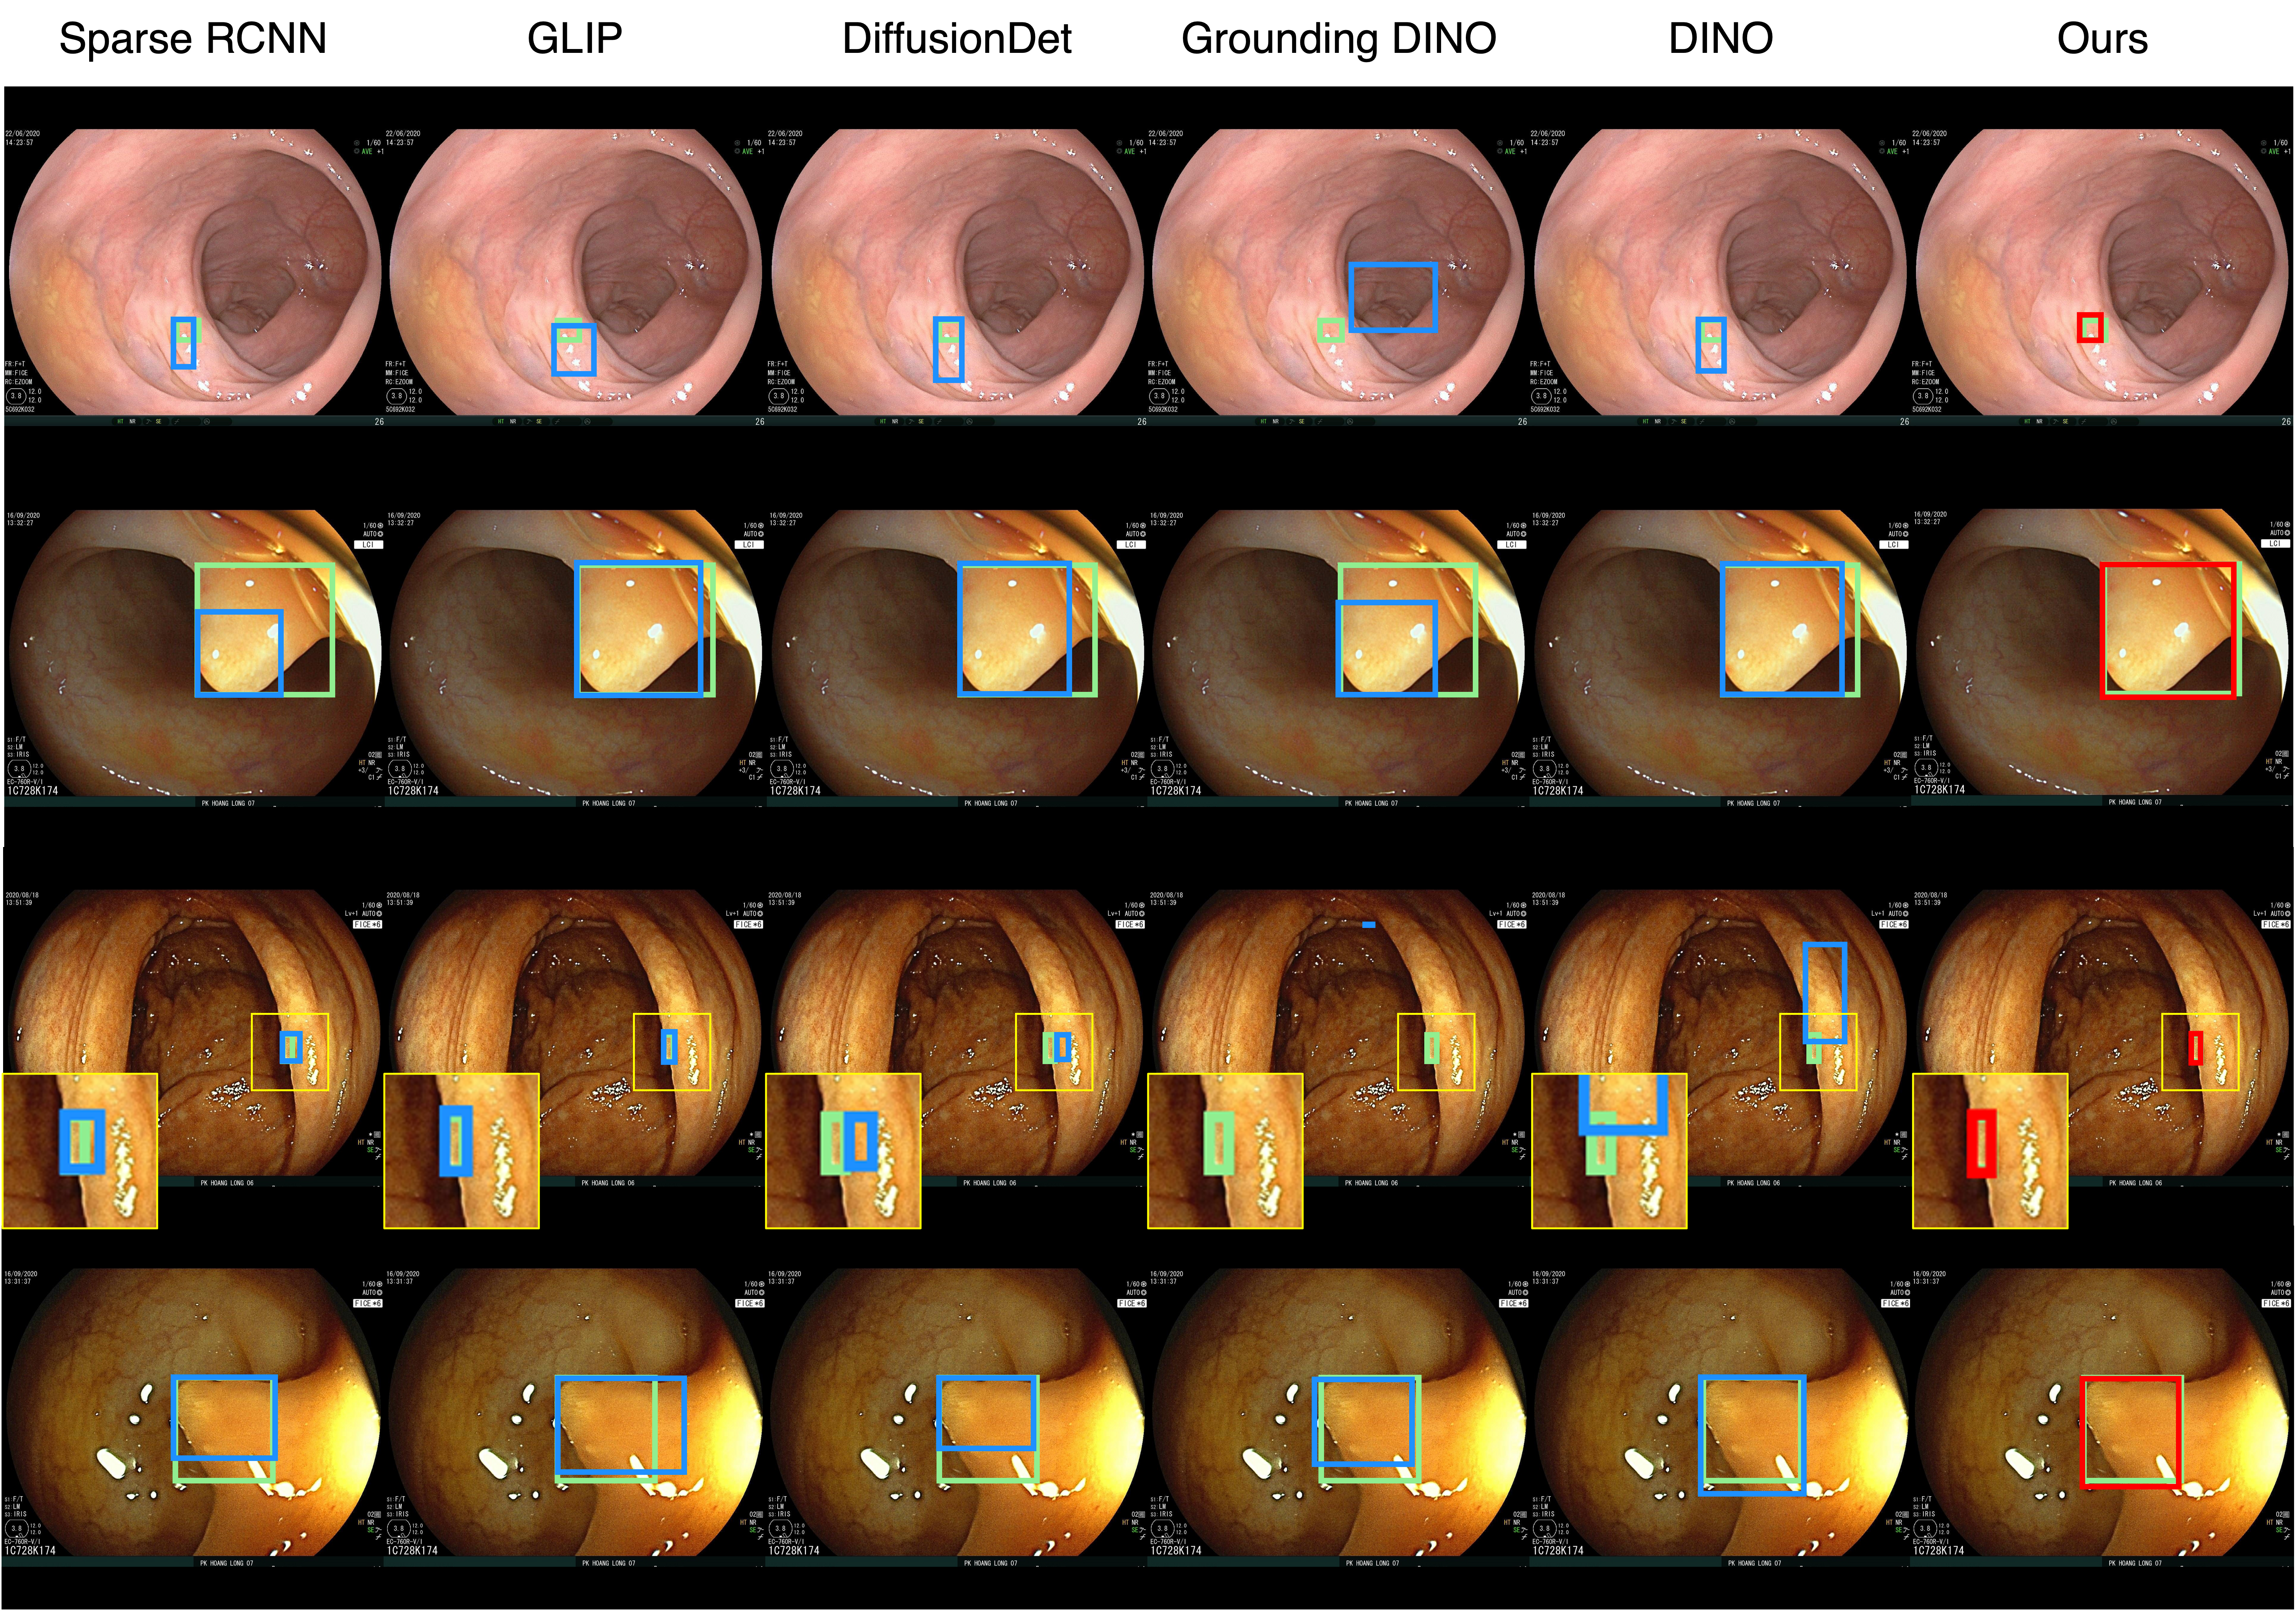

"Neoplastic polyp in colon endoscope"

Qualitative comparison results

Qualitative Comparison. Comparison results between various state-of-the-art detection methods and the proposed method is shown above. Our method effectively leverages modality context to significantly enhance anomaly localization (red), compared to baseline results (blue). Ground truth bounding boxes are green. For cases where the bounding boxes are small, insets show an enlarged view of the highlighted yellow region.